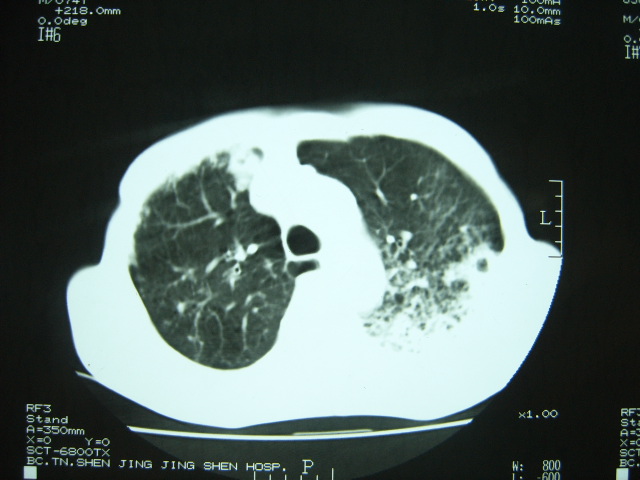

男74岁,咳嗽,寒战,低烧。有糖尿病史。

考虑:1、左下肺脓肿;

2、双肺结核。

考虑:糖尿病合并:1、左下肺炎继发肺脓肿;

两肺结核,左下肺大片实变,内见空洞性病变,壁不规则,结合糖尿病史,考虑:结核性?霉菌性?建议结合实验室检查或治疗后复查。